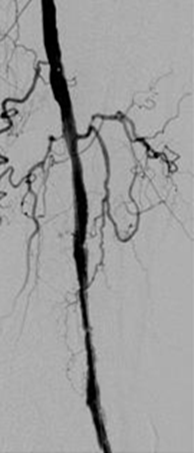

Oclusión de la arteria poplítea distal y del tronco peroneal proximal con arteria peroneal patente y estenosis crítica proximal.